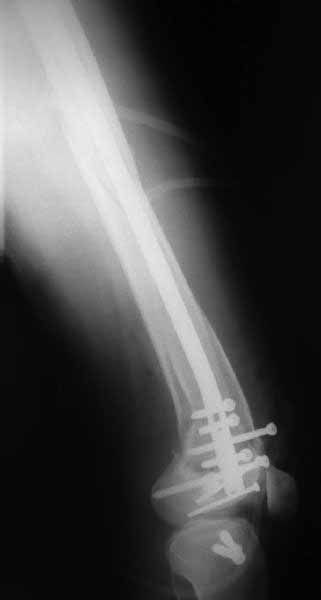

использовать. В приложении пример недавней операции, C3, открытая

репозиция, фиксация мыщелков спицами и винтами, ретроградный синтез

большеберцовым гвоздем 10,5 мм диаметром, винты 5 мм.